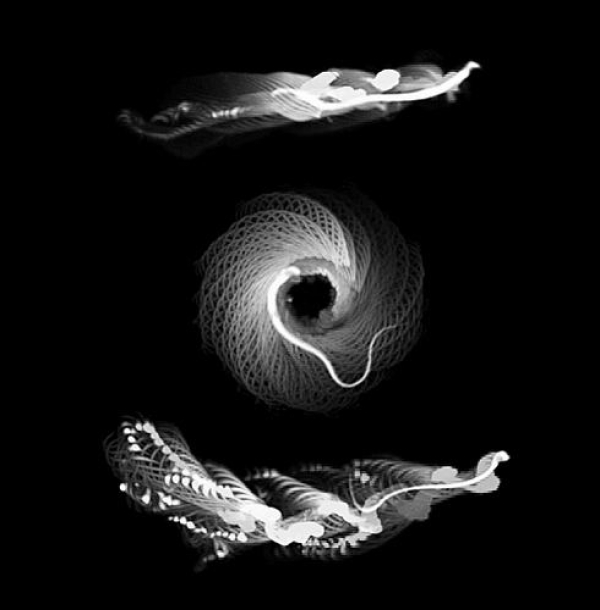

粗浅精子的线性游动旅途(顶部),突变精子的圆形和对角线游动旅途(中部和底部)。图片起首:Gadadhar

讨论东谈主员发现,在莫得这种微管卵白修饰的情况下,鞭毛荒芜的花式受到了滋扰,导致精子大多绕圈游动。该讨论的第一作家、居里讨论所的Sudarshan Gadadhar诠释说:“精子鞭毛的中枢由微管和满坑满谷被称为能源卵白的眇小分子马达构成,后者使有节拍地曲折微管以产生开放成为可能。这些能源卵白的活性必须是邃密合作的。在莫得糖基化的情况下,它们会变得不合作,效果就是看到精子在打转。”

为了找到谜底,讨论东谈主员分析了小鼠模子,在吞吐糖基化的小鼠精子上不雅察到了功能颓势,这导致生养才略着落。为了找出吞吐糖基化为什么会导致精子活力错杂和男性生养才略低下,讨论小组使用冷冻电子显微镜不雅察了鞭毛的分子结构及分子马达。分析清楚,存在突变的鞭毛构建是粗浅的,但突变滋扰了轴突能源卵白的合作步履。这就诠释了为什么精子细胞的游动会受到滋扰。